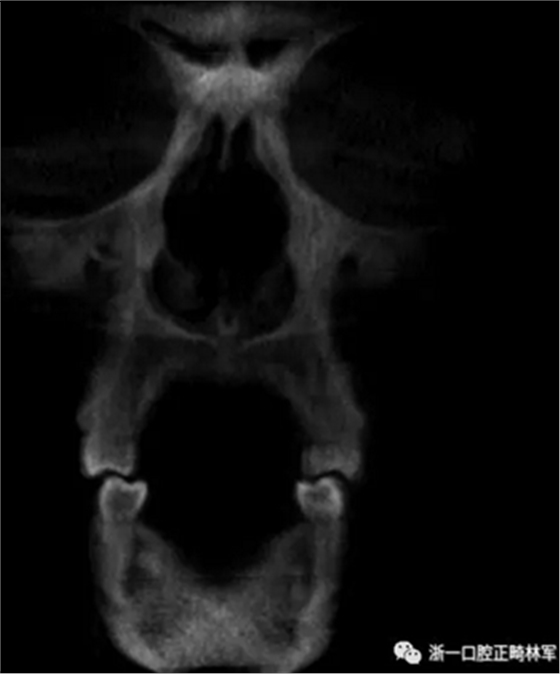

在輸出的3D模型上,使用體內(nèi)軟件(Anatomage,San Jose,Calif)將下頜骨以最小的間隔從顱骨上分離(圖5)用于保留下頜骨的咬合細節(jié),游離的下頜骨被保存(圖6,A)。同時,將沒有下頜骨的顱骨導出并保存(圖6,B)。

圖5. 在磨牙區(qū)域清晰顯示間隔并保留咬合細節(jié)的二維切片。